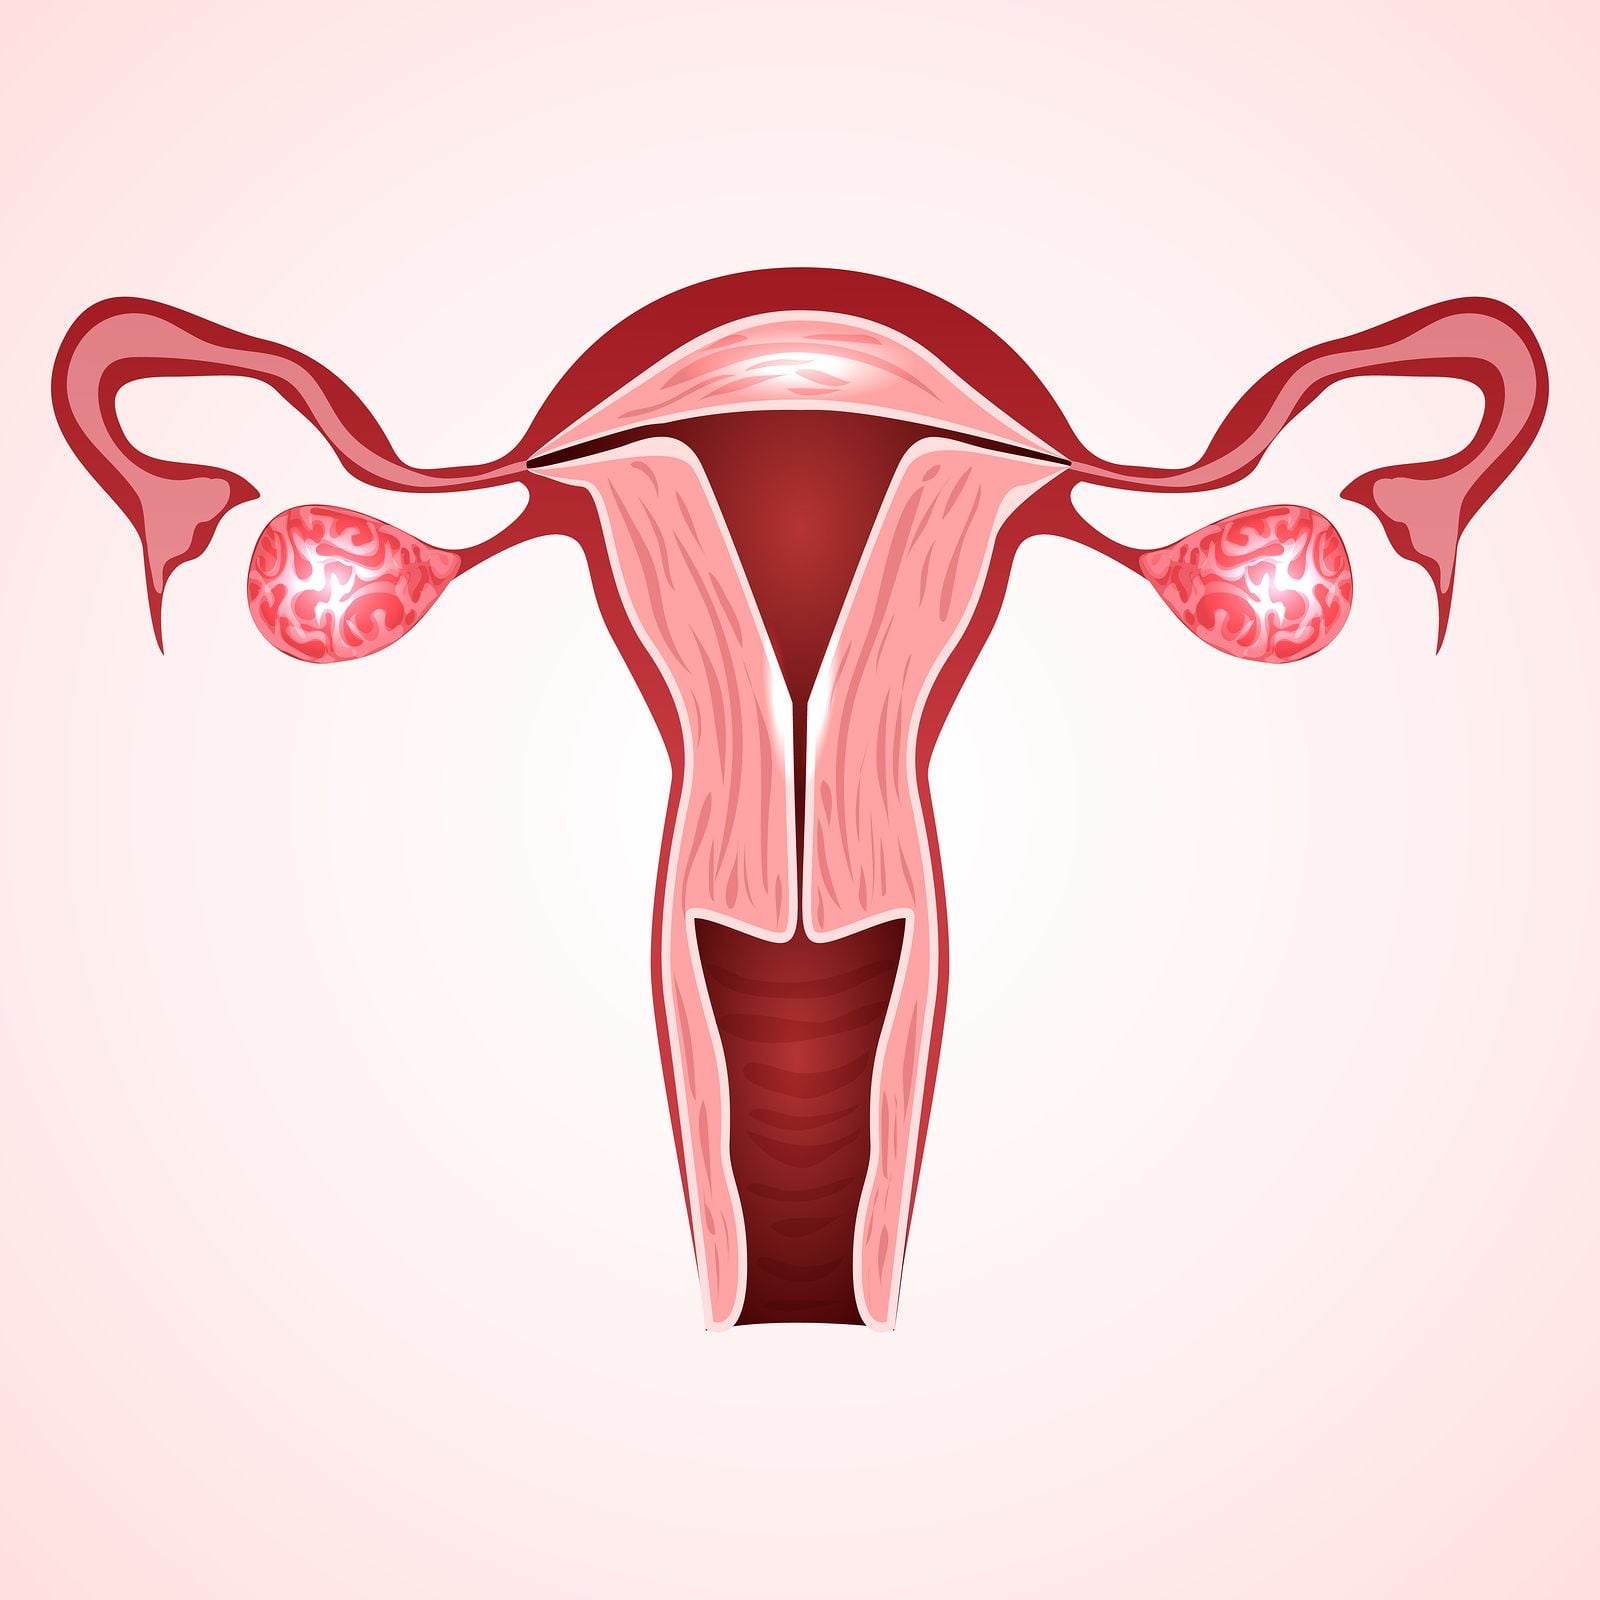

We offer a full spectrum of female and male fertility care, including IVF, egg freezing, genetic screening (PGD/PGS), egg donation, surrogacy and LGBTQ+ fertility. Build your beautiful family with Aspire Fertility.